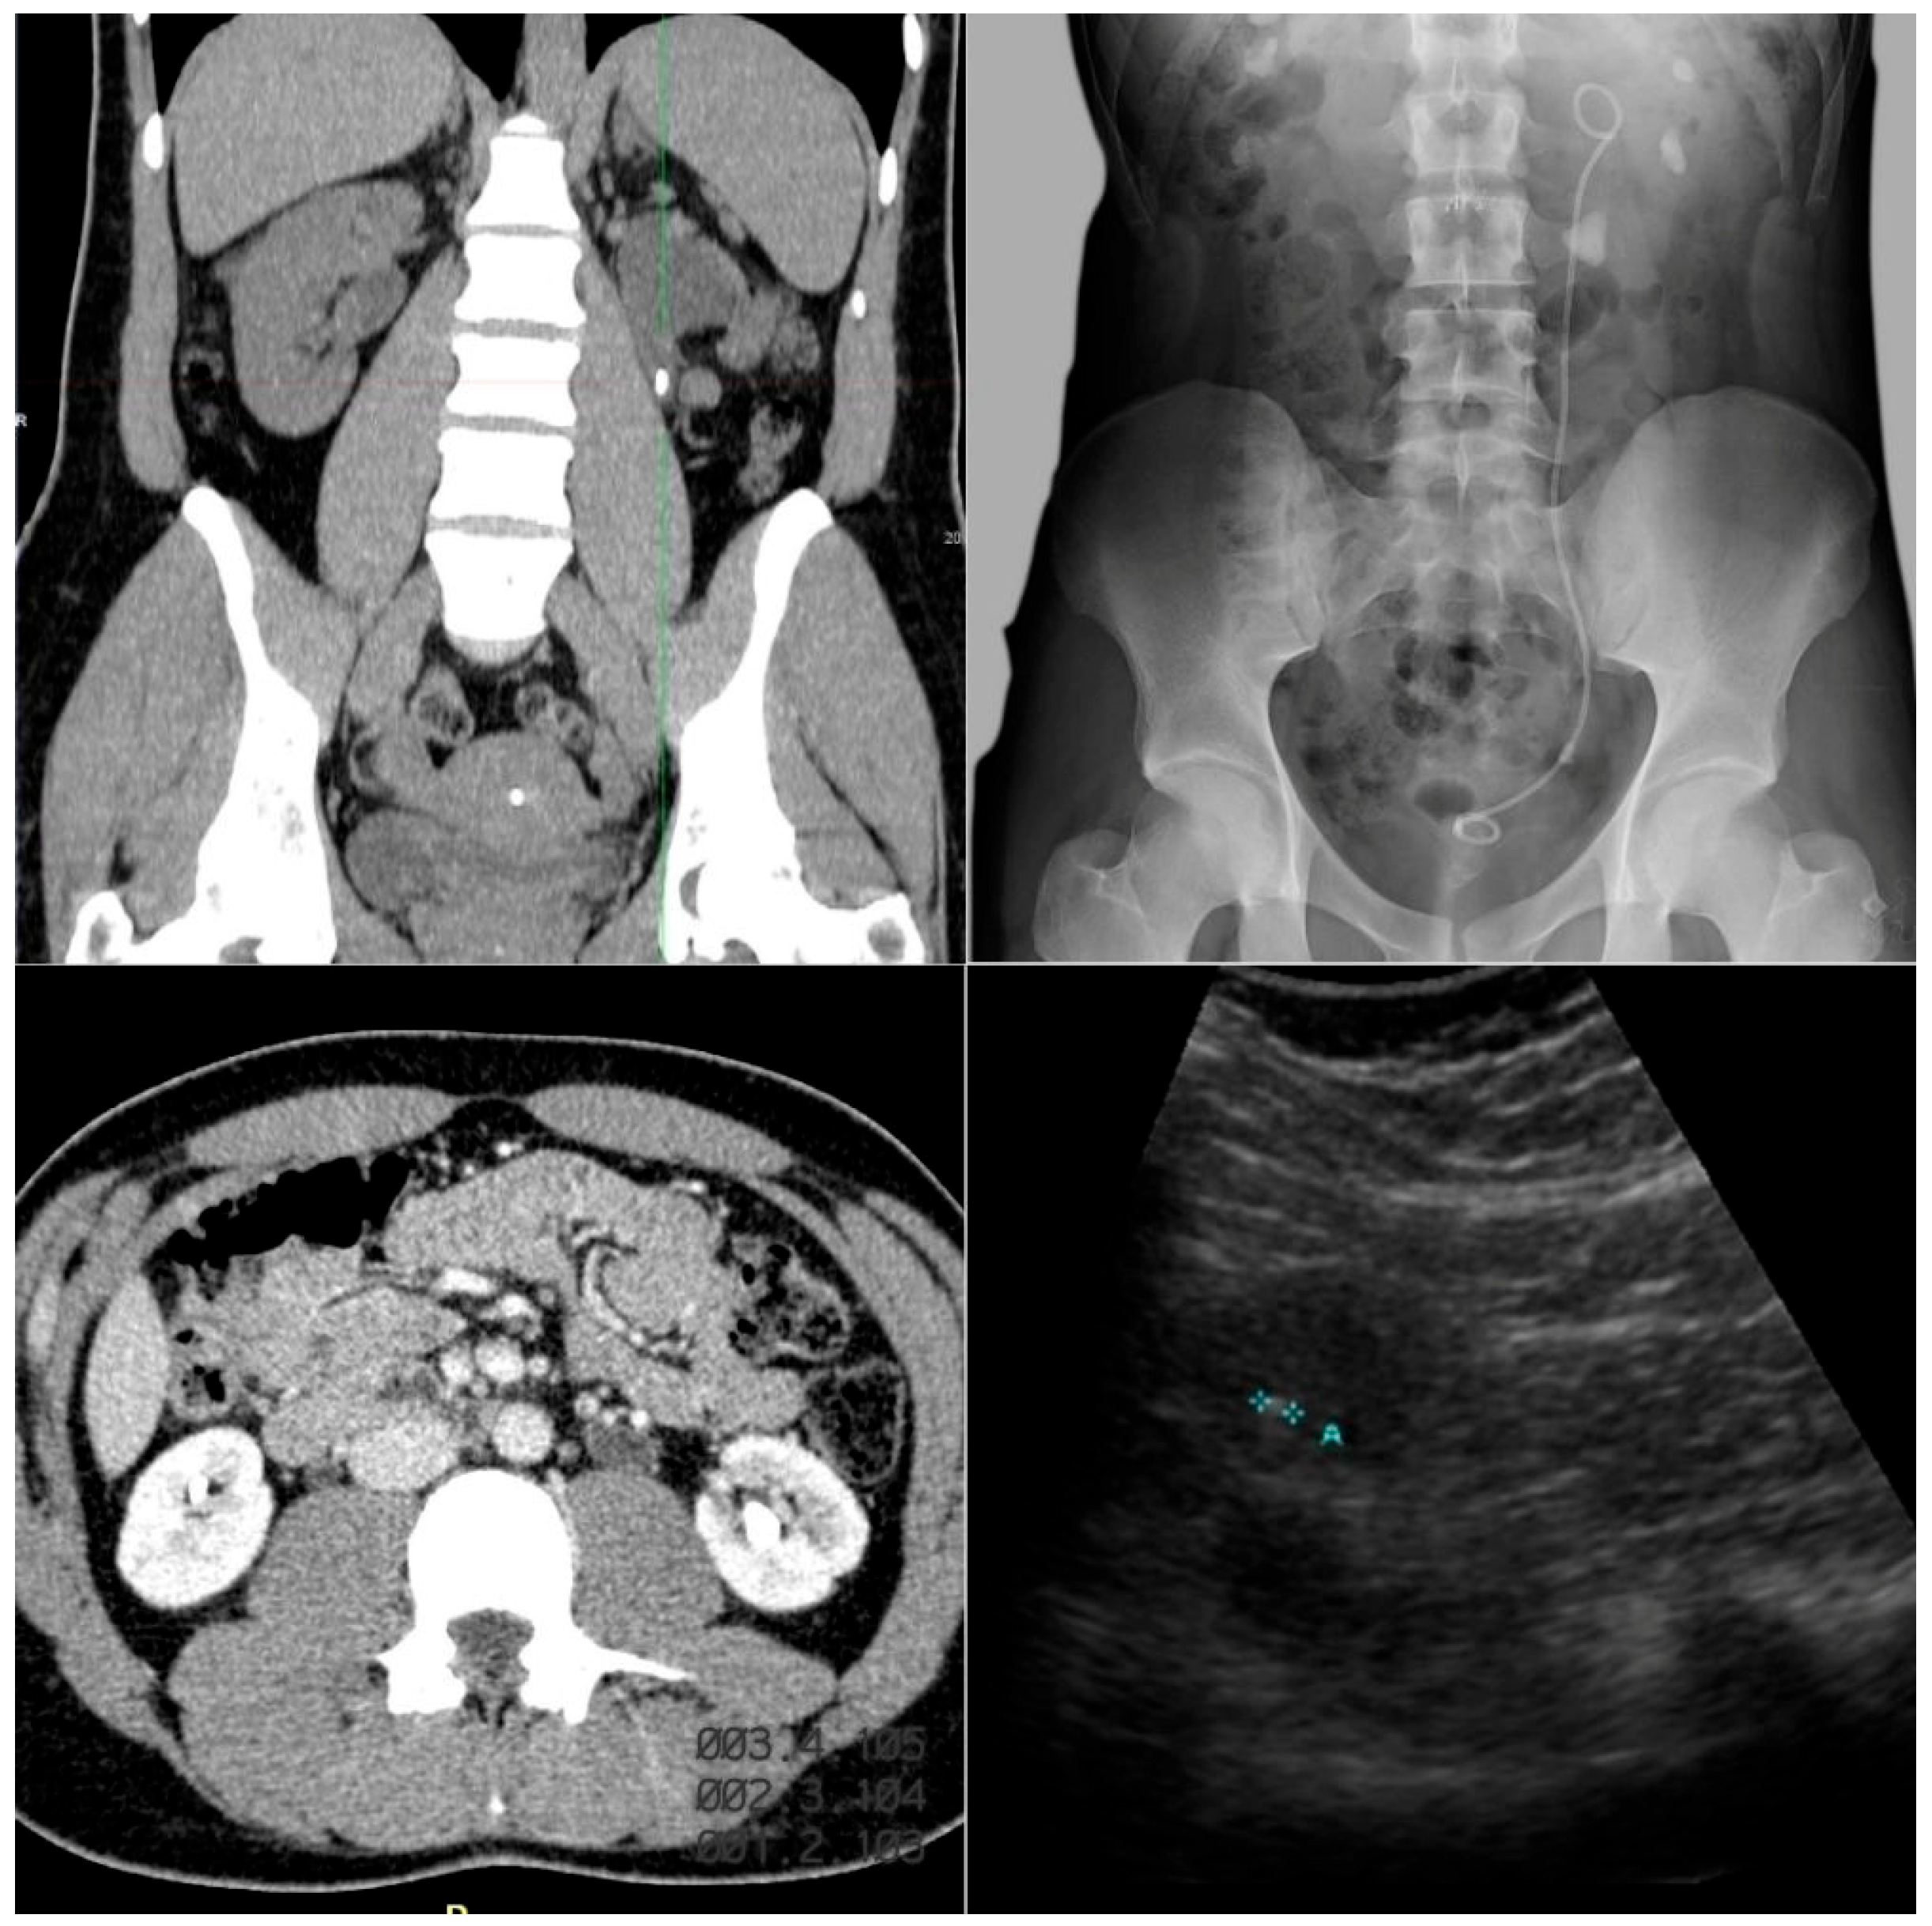

Imaging studies should be performed to detect nephrolithiasis or nephrocalcinosis [24]. Nephrocalcinosis is especially relevant in PH because it reflects higher systemic oxalate load and is associated with a worse renal prognosis [30]. In these patients, CaOx deposition generates diffuse medullary calcifications, often described as “bright papillae” or an “arborescent pattern”, with severity correlating directly with kidney function decline [30,31] (Figure 3).

The main imaging techniques include:

• Ultrasound:

First-line modality due to its safety (no radiation), reproducibility, and low cost. It is particularly useful in children. It identifies calculi in calyces or renal pelvis and detects medullary hyperechogenicity and corticomedullary differentiation loss—typical signs of nephrocalcinosis [31].

• Plain abdominal X-ray:

Serves as a complementary tool in stable patients, often combined with ultrasound. It detects radiopaque stones, and CaOx calculi are commonly visible [32].

• Non-contrast CT:

The gold standard for urinary stone evaluation, with higher sensitivity than ultrasound or intravenous urography. It precisely localizes and characterizes stones, estimates density and composition via Hounsfield Units, and assesses parenchymal calcifications such as nephrocalcinosis [33,34].

Figure 3. Representative imaging of nephrolithiasis in our case series of patients with primary hyperoxaluria in Hospital Universitario La Paz. Computed tomography (left images): coronal section (top) and axial section (bottom) showing hyperdense foci within the urinary system, consistent with urolithiasis. Plain abdominal radiograph (top right): a double J ureteral stent is identified on the left side, associated with radiopaque calcified densities projected onto the renal silhouette, consistent with lithiasis. Ultrasound (bottom right): hyperechoic focus with posterior acoustic shadowing, a characteristic finding of urinary lithiasis.